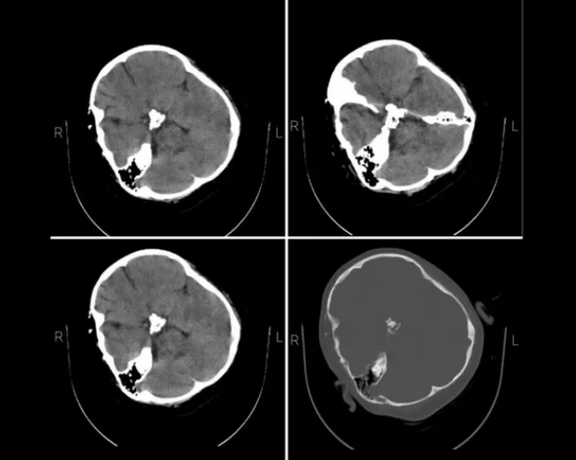

خبرگزاری فارس وابسته به سپاه پاسداران اصالت تصاویر افشا شده از سیتیاسکن مهسا امینی در ایران اینترنشنال را تایید کرد و نوشت که پیگیریهای خبرنگارش از «مراجع ذیربط» نشان میدهد این عکسها مربوط به اوست.